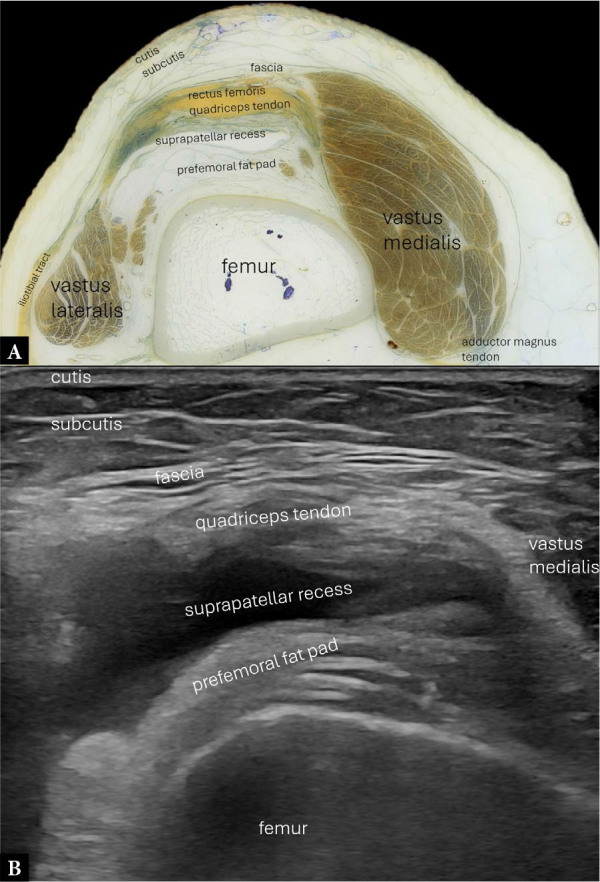

Purpose: To provide an overview of the normal anatomy of the knee using high-resolution ultrasonography.

Materials and methods: Normal ultrasound images were obtained from a healthy subject, and corresponding images of human anatomy and histology were acquired from body donors.

Results: Several high-resolution ultrasound, anatomical, and histological images were created to illustrate and comprehensively describe the basic standard scans in compliance with international standards. This atlas summarizes a selection of typical normal findings.

Conclusions: This overview explains the normal anatomy of the knee as seen by ultrasonography. High-resolution knee musculoskeletal ultrasonography aims to provide an accurate structural evaluation, which requires comprehensive knowledge of sonoanatomy. When used appropriately, contemporary high-resolution musculoskeletal ultrasonography enhances knee imaging by connecting anatomical cross-sections and intricate histology to specific anatomical features.